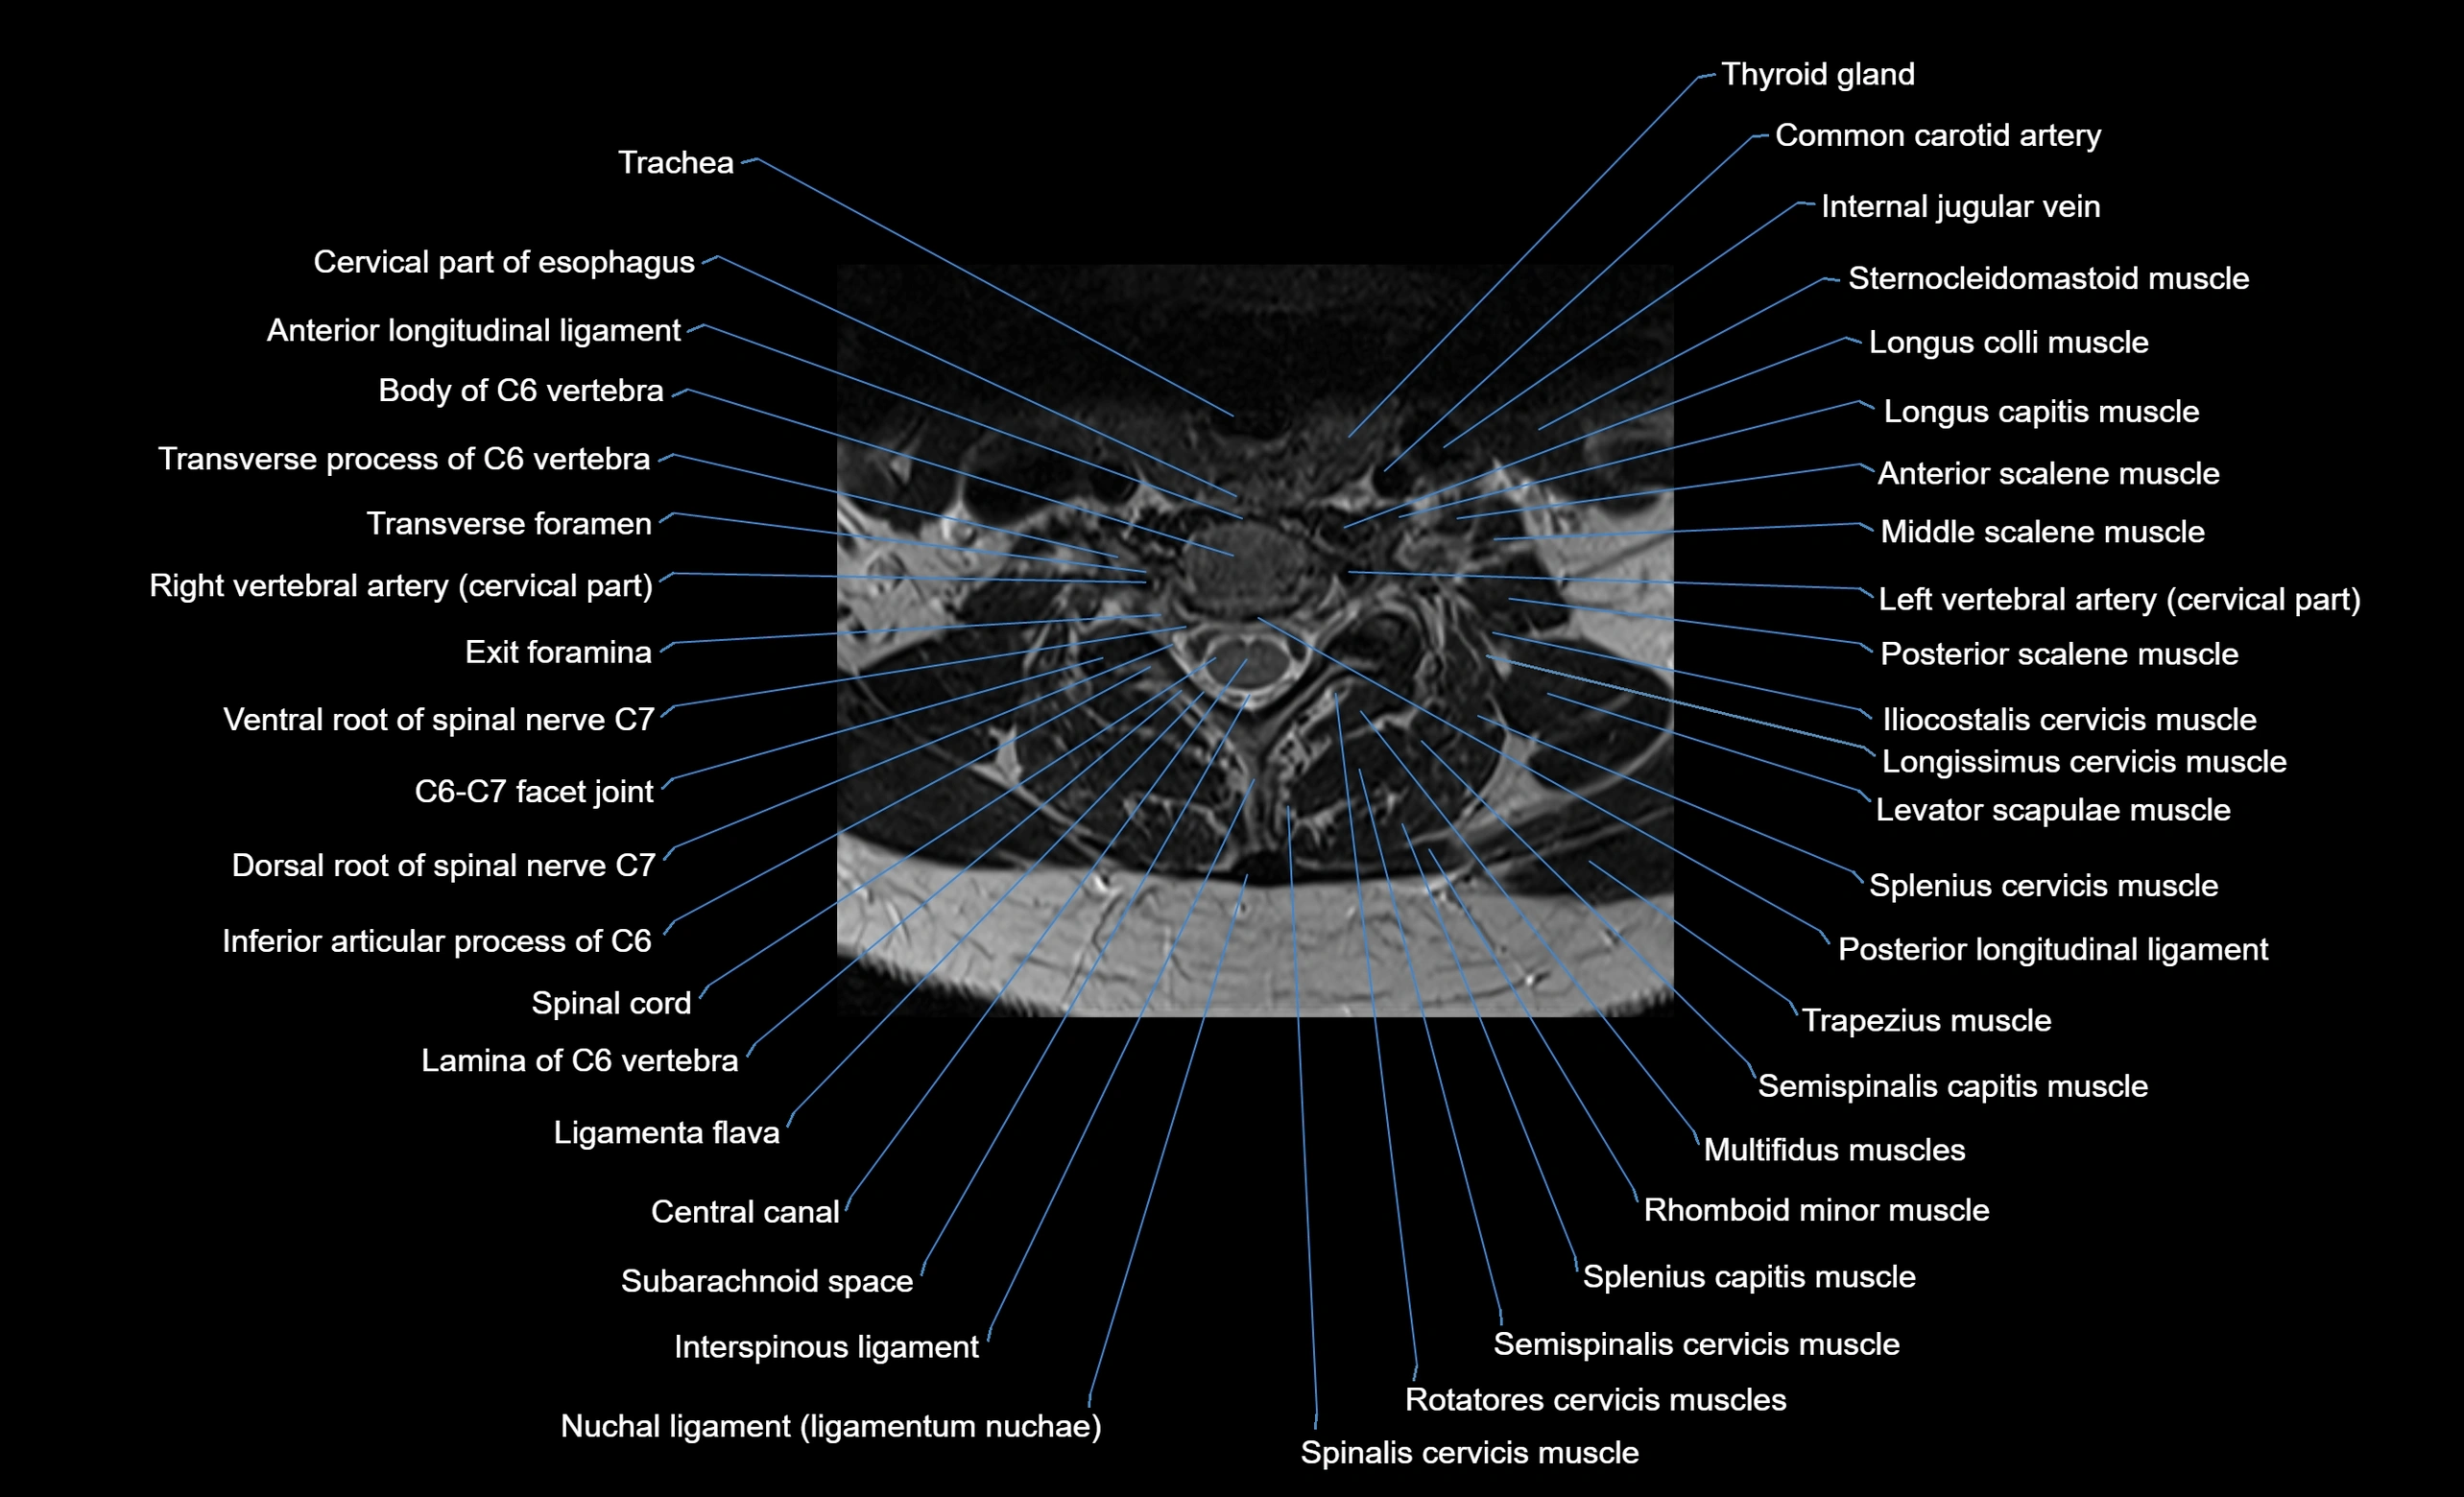

CT appearance

Pre-contrast CT:

• Annular epiphysis: Thin hyperdense bony ring at the vertebral endplate periphery

• Margins: Well-defined cortical outline

• Relationship: Clearly separated from central endplate in skeletally immature patients

• After fusion: Appears continuous with the vertebral body cortex

CT image

image